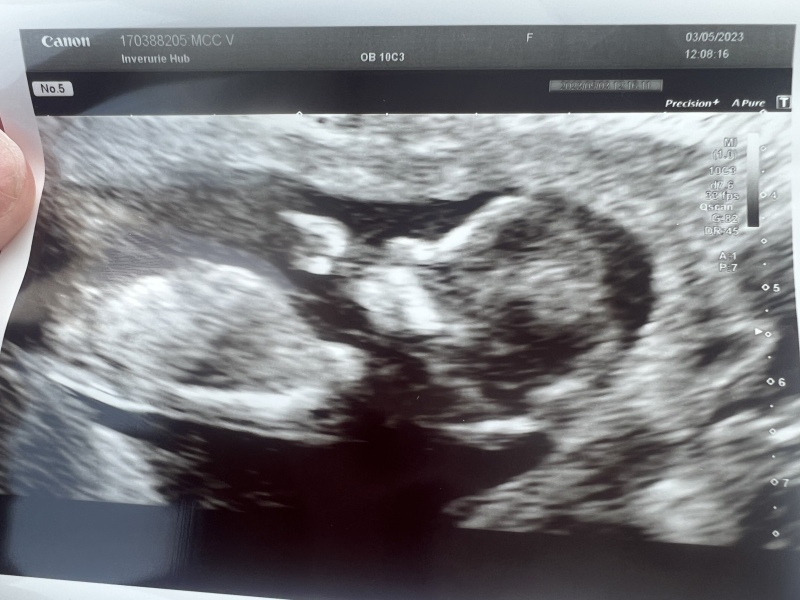

DiamondApricot · 03/05/2023 10:46

Thank you everyone, all is perfect, one healthy bean!

@DiamondApricot amazing!!! How was your dates are whats your official NHS due date? I'm saying little girl 💗

@TTCRainbow thanks, your pics are far more impressive! They've dated me at 12+5 so due date 10.11. My first was 5 days early so I'm hoping for a bonfire night baby.

My nub theory googling also says girl but who knows!

Awww that's a wonderful pic @DiamondApricot so happy all is well ❤️

@DiamondApricot My family and friends who we sent it to said they cant believe how clear my scan is! Not sure why what was but still no nub visible 😫 😂You photo is lovely! I defo think i see a girl nub xx

@Myperfectchaos congratulations due date twin!